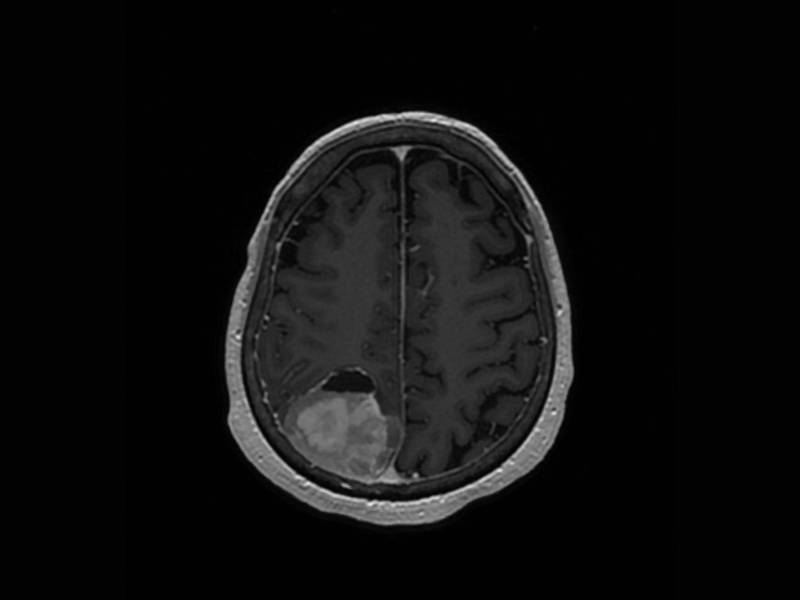

Fotografía referencial de un tumor cerebral.